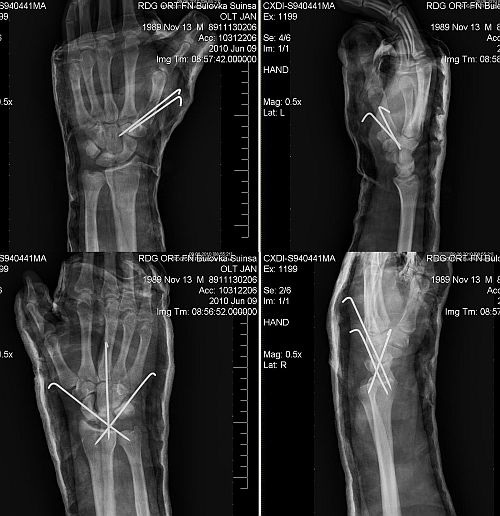

Tak zima ubíhala a pěkný póčo se blížilo. Pořádně nabušit před sezonou. Občas se stane že člověk nesežene spolulezce na stěnu, nu což jsou to lenoši. Já si vystačím, toprope na stěně byly, zavěsím se tada do fixu. Jdu na to, našteluju cinche a lezu si to vostošest. Jedna cesta, druhá cesta, poslední cesta, trocha spěchu, zapomenutej uzlík. Z fixu se stává volný lano. Dolezu nahoru, sednu do cinche. Prsk. Dlouhá tma. Otevřu oči, počítám končetiny. Jsou! Další zatmění. A už to jede - strašná bolest zad, ruce bleskem votejkaj, je mi na blití. Sanitka, kluci sou rychlí, z Bulovky za tři a půl minuty. Nafouknout do vaku a šupšup, rovnou ze sanitky na sál. Verdikt? Polámaných a zlomených osm zápěstních kostí v pravé, vykloubený a rozdrcený palec na levé ruce, zlomený obratel L2 kompres, zhmožděná levá plíce.

2.rtg

foto by © archiv Honza

Tak si nejsem zcela jist , jestli je protekce někdy výhodou. Tímto způsobem se takový úraz ošetřoval před 20lety, nyní jsou již k dispozici minidlahy a šrouby, které umožní mnohem kvalitnější repozici a fixaci zlomenin, dále již také víme, že jsou nějaké vazy zápěstí, které je také nutné ošetřit a nechat jim šanci na zahojení. Nedivím se, že to nefunguje. Vazy zápěstí jsou holt potřeba a tímto způsobem ošetření nedostaly žádnou šanci se zahojit.